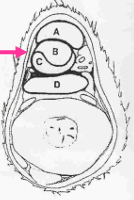

¿De qué zona es este corte? y ¿cuáles son las estrucutras que se ven?

Zona 2B

A - Tendón flexor digital superficial (TFDS)

B - Tendón flexor digital profundo (TFDP)

C - Ligamento frenador (Check Ligament) *Lig frenador envuelve al TFDP

D - Ligamento suspensorio del menudillo (LSM)